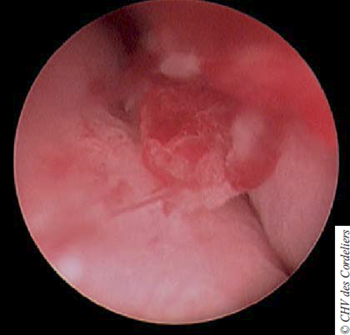

L’endoscopie se poursuit par le cathétérisme urétral ; aucune lésion visible n’est objectivée. L’examen de la vessie ne révèle pas de lésion en regard du trigone. En avant de celui-ci, la présence d’une masse hémorragique occupant la quasi-totalité de la lumière vésicale est confirmée.

Des biopsies étagées (vessie, urètre et vagin) sont réalisées. L’histologie permet d’établir le diagnostic de carcinome peu différencié à cellules transitionnelles infiltrant au moins le chorion.